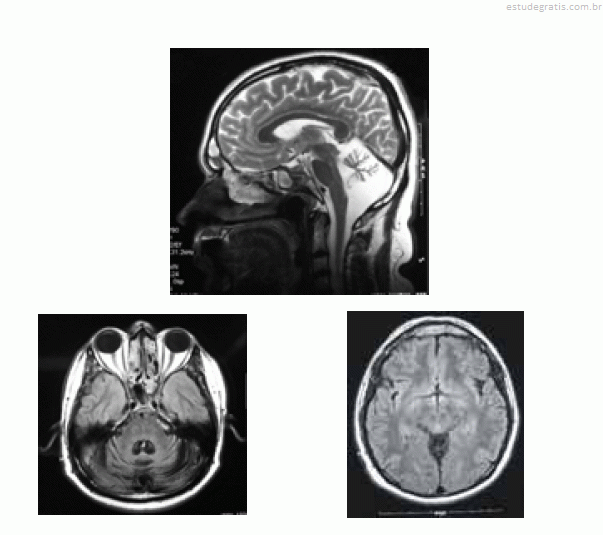

José, com 42 anos de idade, foi renovar sua carteira de motorista e, ainda na entrada do consultório, o médico observou uma marcha com base alargada e insegura. Durante a avaliação clínica, ao testar a coordenação, o médico verificou tremor de intenção à prova índex-nariz, dismetria e disdiacocinesia bilateral. Os pares cranianos, a força muscular e os reflexos — profundos e superficiais — eram normais. A fala de José era pausada, silabada. Ao ser questionado sobre o uso de álcool, negou-o e referiu que o problema do desequilíbrio vem piorando nos últimos dez anos, fato que provocou o acompanhamento médico e motivou a realização de uma ressonância nuclear magnética (RNM), cujas imagens são apresentadas abaixo.

A RNM evidencia uma atrofia cerebral grave, que é compatível com os sintomas descritos.